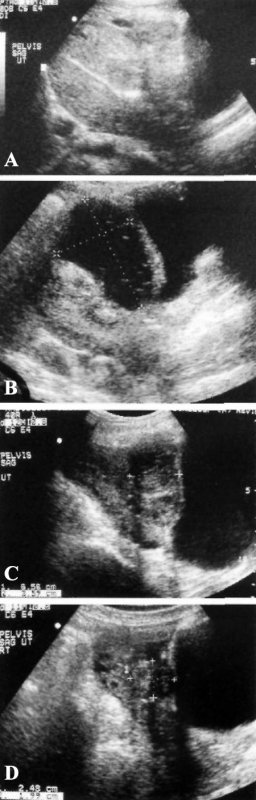

Кесарево сечение подразумевает рассечение тканей с целью доступа в экстраперитонеальное пространство между передней частью нижнего сегмента матки и задней частью мочевого пузыря, таким образом обеспечивая доступ для проведения нижнего поперечного разреза стенки матки. Именно в этой области часто образуются гематомы разного размера – так называемые «гематомы пузырного лоскута», – которые на УЗИ и КТ визуализируются как гетерогенные скопления (фото 3). Нужно отметить, что в таких случаях гематома может распространяться под серозным покровом вокруг матки, вдоль широкой связки и проникать в забрюшинное пространство.

УЗИ: Гематома пузырного лоскута

Фото 3. Гематома пузырного лоскута. А – УЗИ в сагиттальной плоскости: определяется гетерогенное скопление между нижним сегментом матки и мочевым пузырем на 3-й день после кесарева сечения. В – УЗИ этой же пациентки через 5 недель: отмечается разрешение гематомы. С – через 3 месяца. D – через 6 месяцев